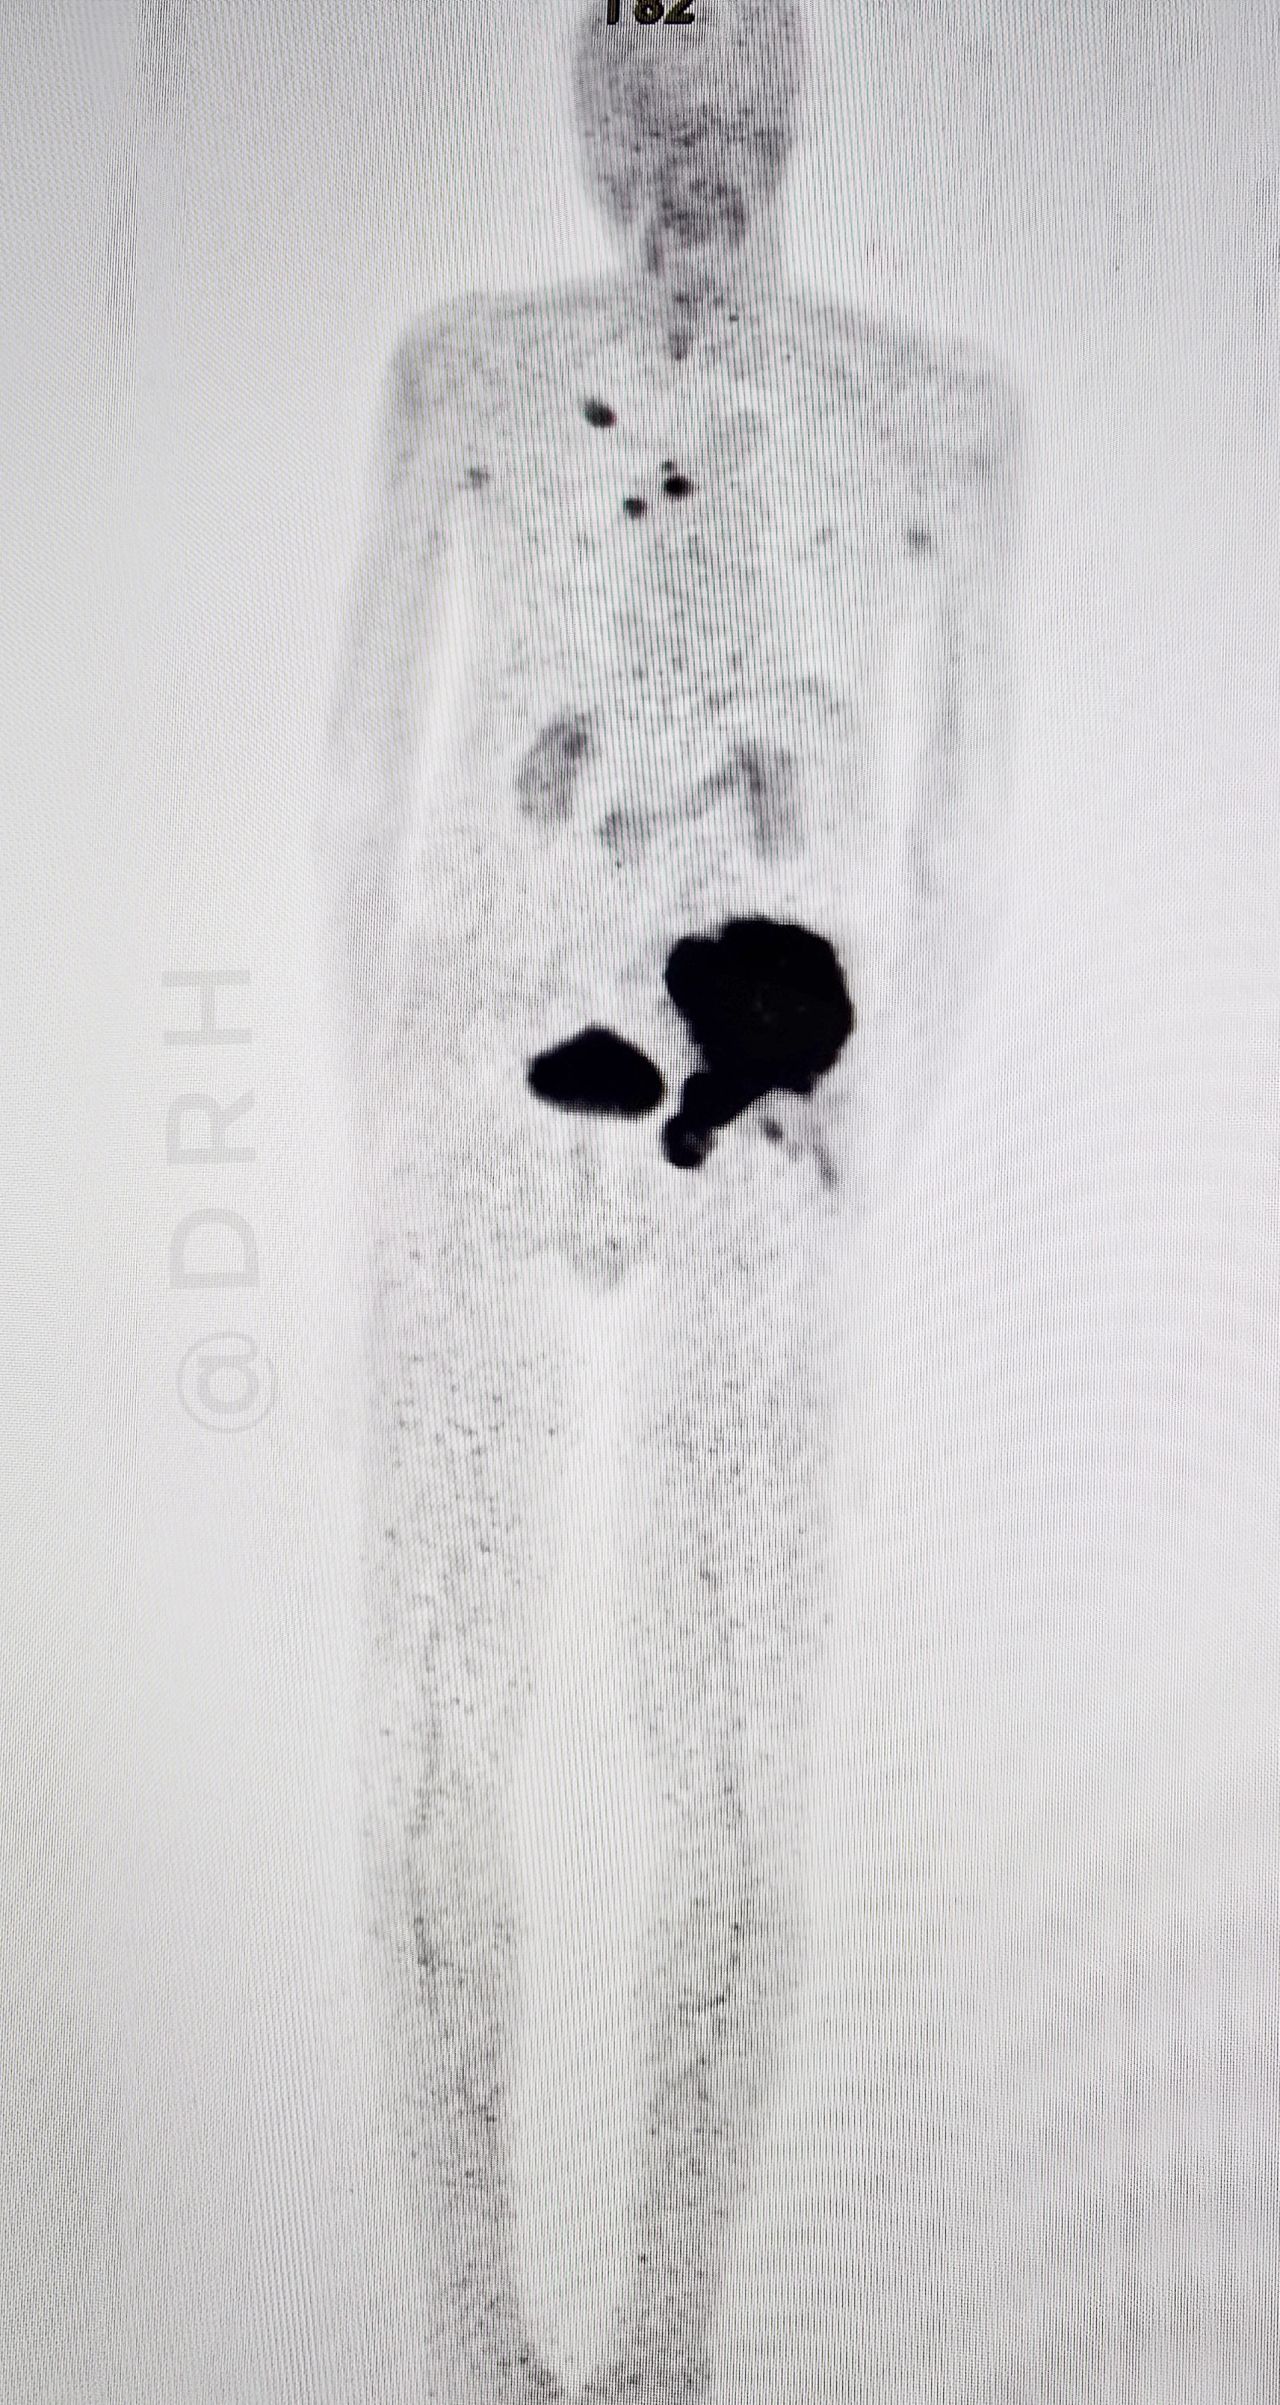

“We recently encountered a case of left iliac bone lytic lesion detected on CT scan highly suspicuous for malignancy who was sent for PET-CT to identify the primary tumor.

A FAPI PET-CT scan was performed, which revealed a primary lung lesion in the right upper lobe along with mediastinal lymph node metastases, confirming the diagnosis of metastatic lung cancer.

– One of the unique advantages of FAPI PET-CT is its lack of physiological uptake in the brain, which allows for clear detection of brain metastases.Consent- Taken before posting the images.”